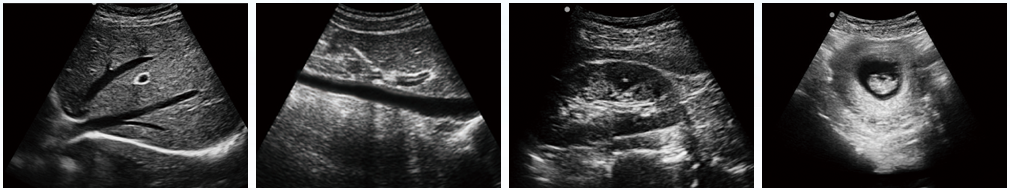

設(shè)備用途說(shuō)明:主要應(yīng)用于腹部、淺表組織、生殖系統(tǒng)、泌尿系統(tǒng)等器官的檢查

全數(shù)字成像技術(shù),真實(shí)、細(xì)膩地顯示組織結(jié)構(gòu);